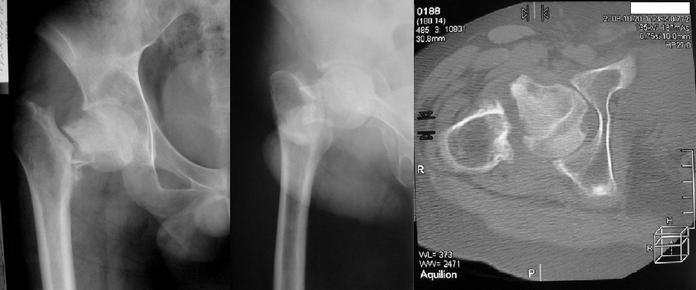

Уважаемые коллеги! Пациент 21 года, травма год назад, в настоящее время ходит с тростью, беспокоит умеренная боль, хромота. Сопутствующая патология - шизофрения, на первый взгляд вполне компенсирован, но кто его знает, что там у него в душе творится. Стоит ли протезировать? Сопутствующая патология - шизофрения, на первый взгляд вполне компенсирован, но кто его знает, что там у него в душе творится. Стоит ли протезировать? Поделитесь опытом выполнения подобных операций у шизофреников, как оно в послеоперационном периоде? Может быть лучше выполнить что-нибудь паллиативное типа медиализирующей остеотомии по McMurrey? Или вальгизирующую остеотомию с клинковой пластиной? Или вообще ничего не делать, оставить человека в покое?

Dear colleagues! 21 year old male injuried one year ago. At present he can walk with cane, suffering from moderate pain and limp. He have a schizophrenia as concomitant disease. It seems to be compensated, but who can say what is in the back of his mind? Is it worth to perform arthroplasty? Please share your experince of such surgery in schizophrenics! What is it in postoperative period? May be any palliative surgery is preferred in this case? Like as medializing osteotomy according to McMurray or valgus osteotomy with blade-plate fixation? May be it's worth to abstain from any surgery and leave patient in this state?